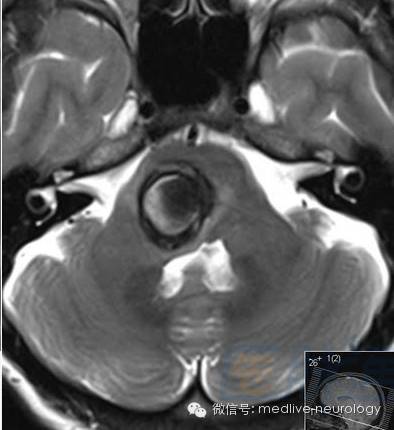

然后解决第三个问题,轻松一下,图来啦,让我们巩固一下今天学习的成果,均为先T1,后T2。

亚急性早期(3-7d): 脑桥